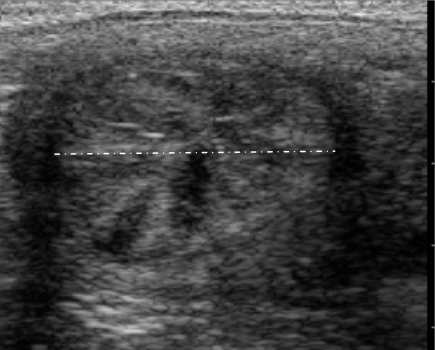

【子宫角的横截面(发情期);没有液体滞留,也没有分界层】

马子宫角发情横截面